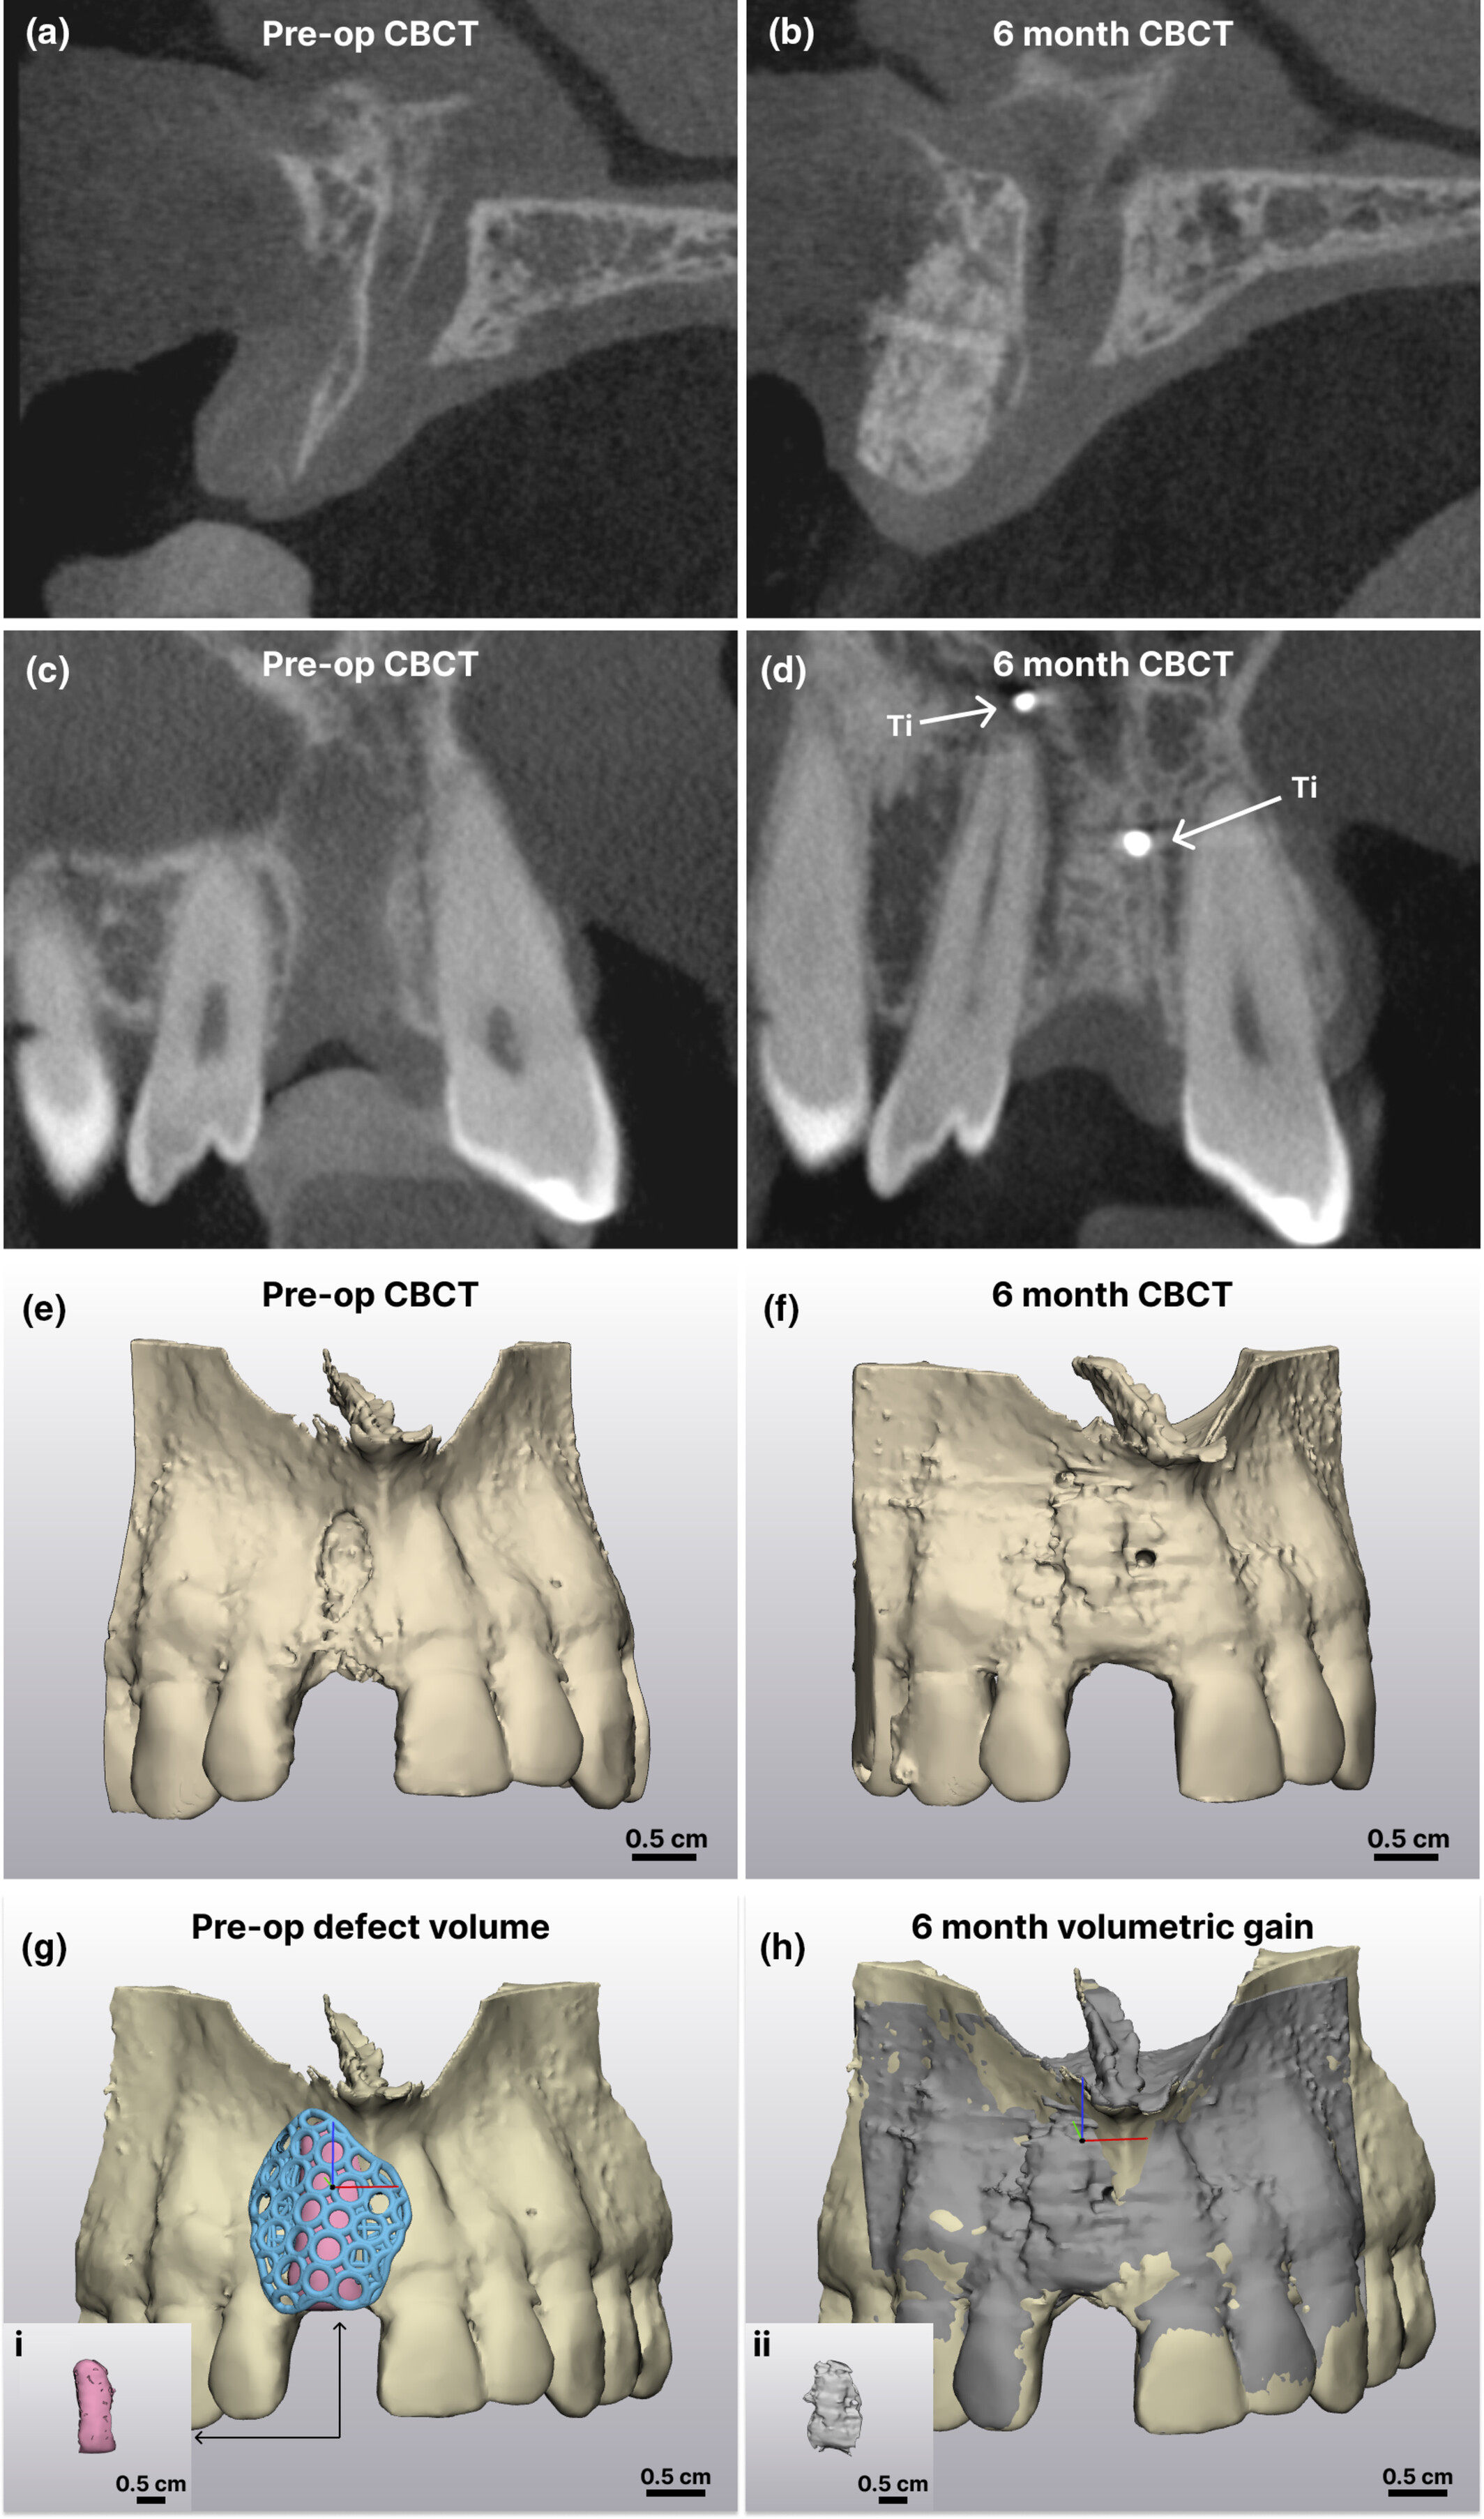

△案例中患者术前 GBR

CBCT 与 6 个月愈合后的X 射线图像比较。 (a 和 c) 术前矢状面和冠状面横截面;(b 和 d) 术后 6

个月矢状面和冠状面横截面;(e 和 f) CBCT 图像的 3D 重建(术前和术后 6 个月);(g) 术前缺损体积;Ti,钛固定螺钉;(i)

粉色体积代表支架下方没有骨骼的区域;(h) 6 个月体积增加;(ii) 灰色体积的分割代表通过布尔减法得到的术前和 6 个月 CBCT

之间的差异。比例尺 = 0.5 cm。